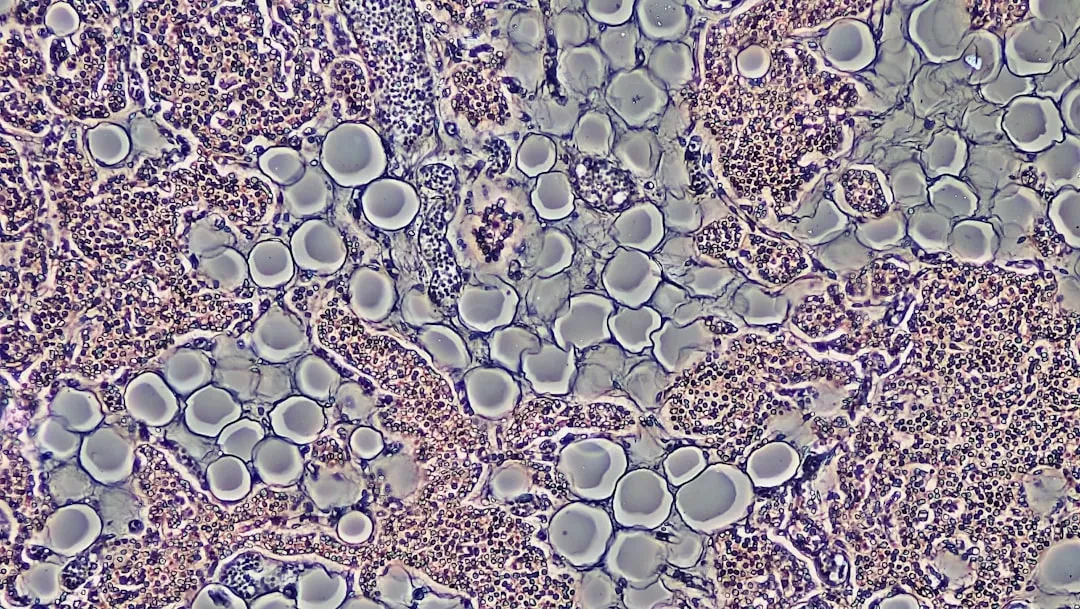

Cellular Senescence: Clearing Out The “Zombie” Cells

One of the biggest villains in the aging story is something called cellular senescence. These are cells that stop dividing because of damage or stress but stubbornly refuse to die. Instead, they sit there like tiny biological zombies, oozing out inflammatory signals that harm healthy neighbors and contribute to arthritis, heart disease, and even some cancers. As we get older, these senescent cells build up, like rust spreading quietly through a machine.

In mice, clearing out senescent cells using drugs known as senolytics has extended healthy lifespan and improved physical function. Several early-stage human trials are now testing senolytics for conditions like lung fibrosis and kidney disease, trying to see whether “zombie cell” cleanup translates into real benefits. It’s not immortality, but if you imagine aging as a car that slowly fills with junk, then senolytics are like a cleanup crew – crucial, but only one part of the repair job.